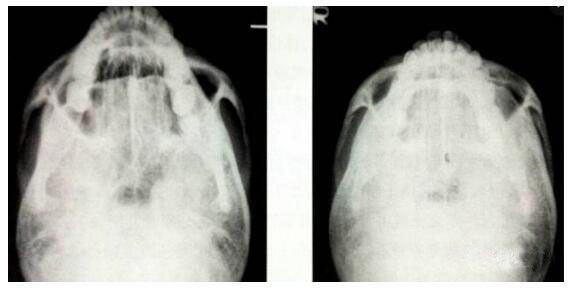

這個(gè)手術(shù)方法創(chuàng)傷比較小,恢復(fù)比較快。術(shù)后三個(gè)月內(nèi)注意不要強(qiáng)力壓迫顴弓處,手術(shù)果,X線片也顯示顴弓內(nèi)收的果顯著▼

圖 / 微創(chuàng)法顴弓內(nèi)推手術(shù)的X線片術(shù)前、術(shù)后的果比較